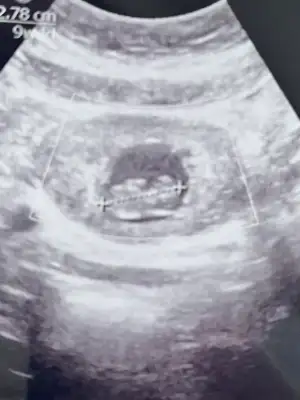

Ay benimde 12 +1 bana da tahminde bulunabilir misinizKız gördüm sanki, sağlıcakla gelsin

Yüz üstü durmuş sankiAy benimde 12 +1 bana da tahminde bulunabilir misiniz![]()

Evet yüz üstü yatıyor o yüzden doktorda bişey diyemedi belki sizin bi tahmininiz vardır diye sormak istedimYüz üstü durmuş sanki![]()

Belli oldu mu cinsiyetinizBende sizinle ayniyim 13+2 cuma günü gideceğim bakalım ne diyecek

Yok canım ya inşallah bir dahaki sefere düzgün pozisyon alır minik kuşEvet yüz üstü yatıyor o yüzden doktorda bişey diyemedi belki sizin bi tahmininiz vardır diye sormak istedim![]()

İki çizgi olması kız ama nub'u bir tık yukarı doğru erkek mi acaba derken kız yerine erkek yazmışımnub'u dik de olsa o çizgiler birbirinden ayrı olursa %90 kız oluyor

Annenin içine doğan olur genellikle, benim size cinsiyet tahminim de kıızBen hep kız hissettim hiç beklemiyordum açıkçası sürpriz oldu bana daama detaylı ultrason da farklı çıkabiliyormus onu da bir bekleyelim dedi doktor değişme ihtimali olur mu hiç bilmiyorum ama

Doktor çok emindi aslında kesin dedi ama ben emin olamayınca öyle dedi bakalım sağlıklı olsun daAnnenin içine doğan olur genellikle, benim size cinsiyet tahminim de kıızilk başta erkek diye yanlış yazmışım